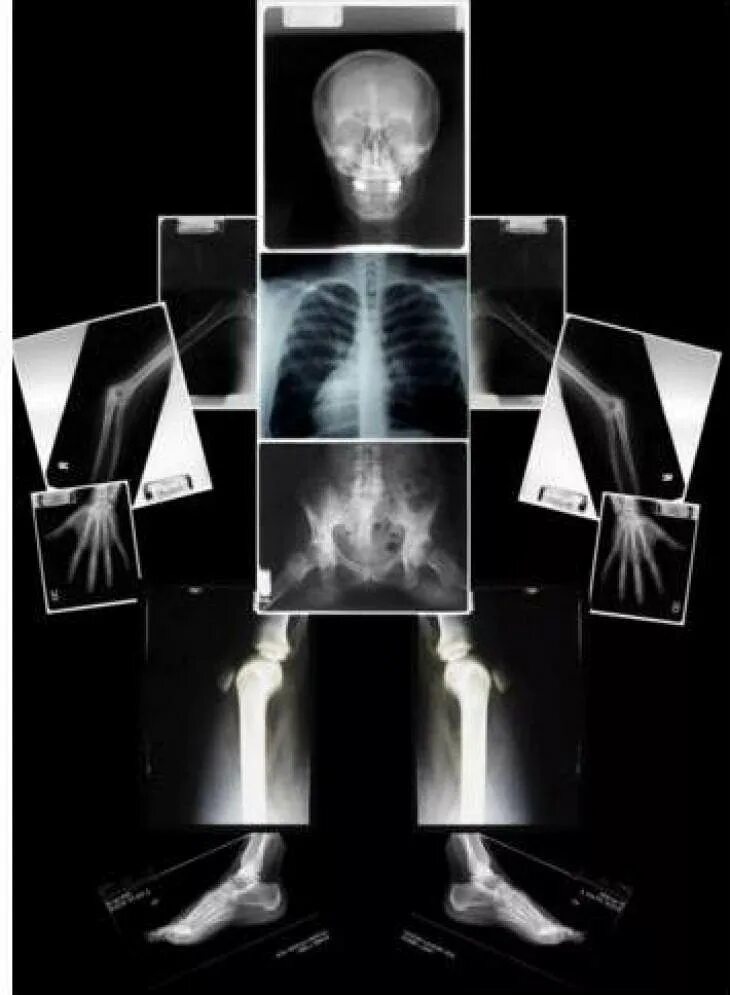

Как прочитать снимок